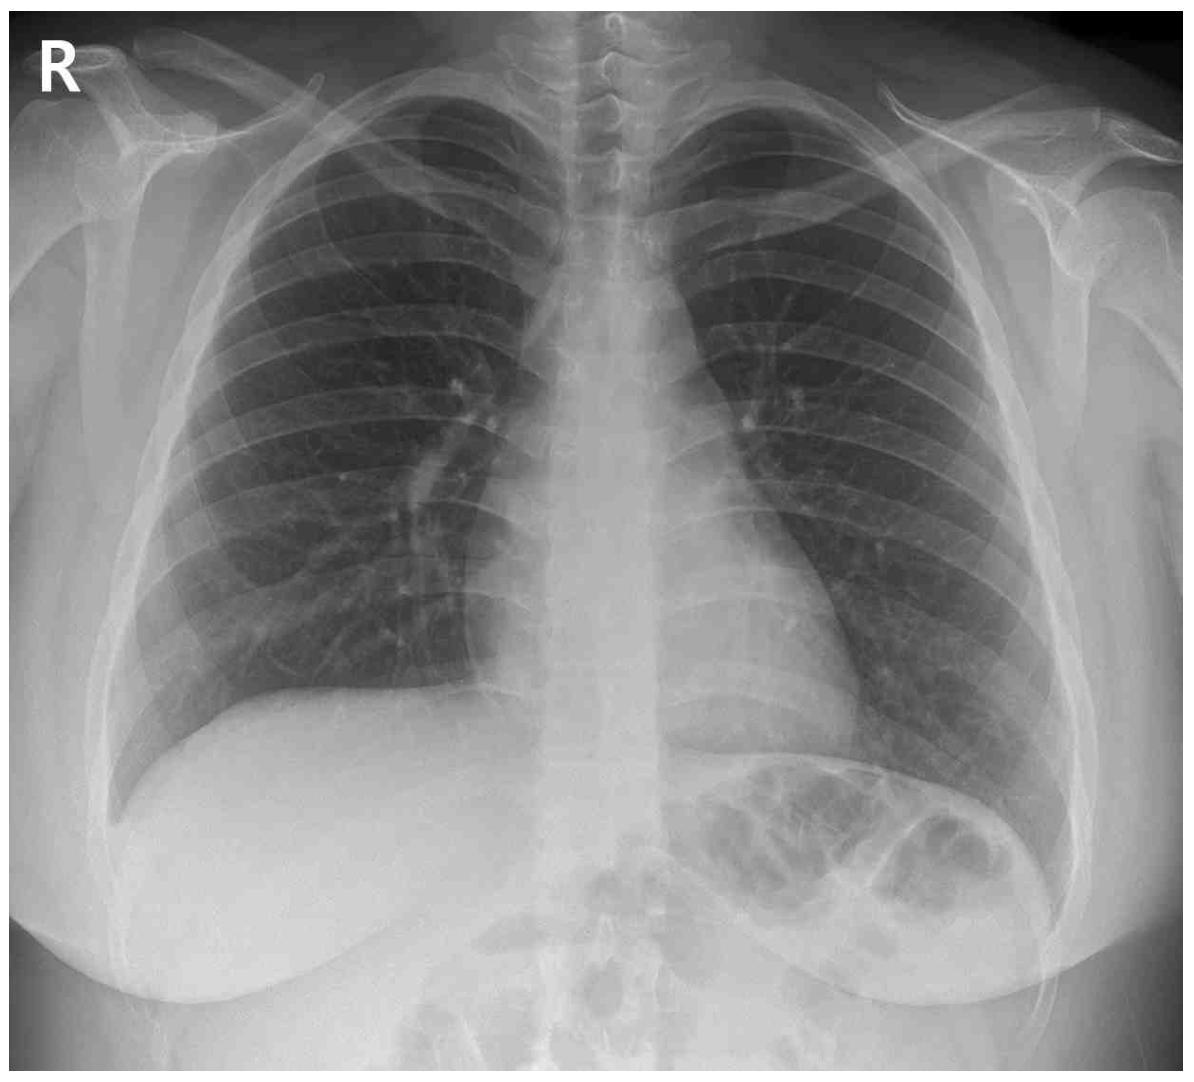

20세 여자가 1시간 전부터 왼쪽 가슴이 아프다며 병원에 왔다. 가슴통증은 숨을 깊이 들이쉴 때 더 심하다. 기침과 가래는 없다. 비흡연자이다. 혈압 120/70 mmHg, 맥박 78회/분, 호흡 20회/분, 체온 36.8℃이다. 왼쪽 가슴에서 촉각진동감과 호흡음이 감소되어 있다. 가슴 X선사진과 심전도이다. 진단은?

CXR: No remarkable findings

Imp: R/O 기흉(pneumothorax, 공기가슴증)

급성으로 발생한 좌측 가슴통증에 대해 보기 중 기흉이 가장 적절한 정답이다.

• 가슴통증은 숨을 들이쉴 때 악화되는 pleuritic pain의 양상으로 흉막 삼출, 기흉, 폐색전증 등의 질환을 고려하여야 한다.

• 신체 진찰상 왼쪽 가슴의 촉각진동감 및 호흡음이 감소되어 있으므로 해당 부위에 발생한 기흉, 흉막 삼출, 무기폐를 의심해야 한다. 현재 CXR상 양측 CPA blunting이 저명하지 않으므로 흉막 삼출로 인한 통증은 배제할 수 있다.

• 보기에 주어진 질환들 중 기흉이 가장 의심되지만, CXR에서 pleural line과 distal pulmonary vascular marking의 소실이 저명하게 확인되지는 않는다. 기흉이 CXR에서 보이지 않을 정도로 작거나, 문제에서 주어진 사진의 화질이 좋지 않은 것으로 추정된다.

• 가슴막삼출: CXR상 CPA blunting이 관찰되지 않으므로 배제할 수 있다.